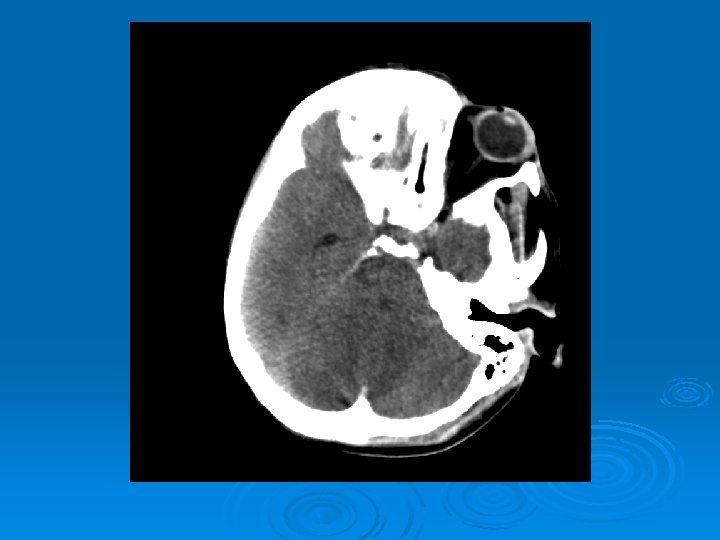

Course: Ø 3 PM, RN noticed anisocoria and L pupil non-reactive. Ø Neurology STAT dose mannitol and w/ dilantin. Ø Pt went for stat head Ct:

CT head 2/11/07 Ø A right frontal ventriculostomy catheter Ø Diffuse sulcal effacement with thickening of the cortex. Ø Loss of gray-white differentiation and hypodensity in the left parietooccipital region. Ø There is diffuse hypodensity of the cerebellum and brainstem. Ø Ø Ø The basilar cisterns are nearly completely effaced. Ø Impression: Ø Worsened diffuse cerebral edema The lateral ventricles are smaller

Course: Ø Neurosurgery saw pt: on exam she had lost cough, gag reflexes, corneal reflexes, she had flexed RUE, semipurposeful with bilateral extended LE. Ø Concern for herniation: placed Ø ICP 35 -40 10 th-11 th EVD